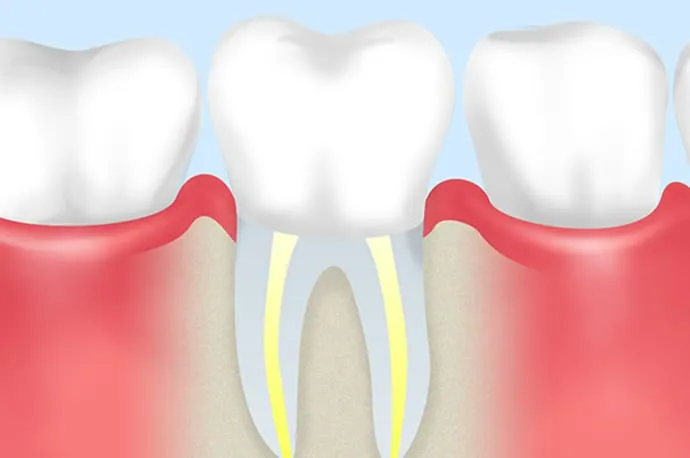

根管治療とは

虫歯が重度に進行すると、虫歯菌が歯の神経まで感染し、歯の内部にある神経を取り除く必要が出てくることがあります。

根管治療とは、文字通り「歯の神経が入っている根の管(根管)」に対して行う治療です。もし根管治療を行わずに放置してしまうと、細菌が歯の根の先にたまり、やがて根の先が化膿してしまいます。その結果、強い痛みが出たり、歯ぐきや頬が腫れたりすることもあります。